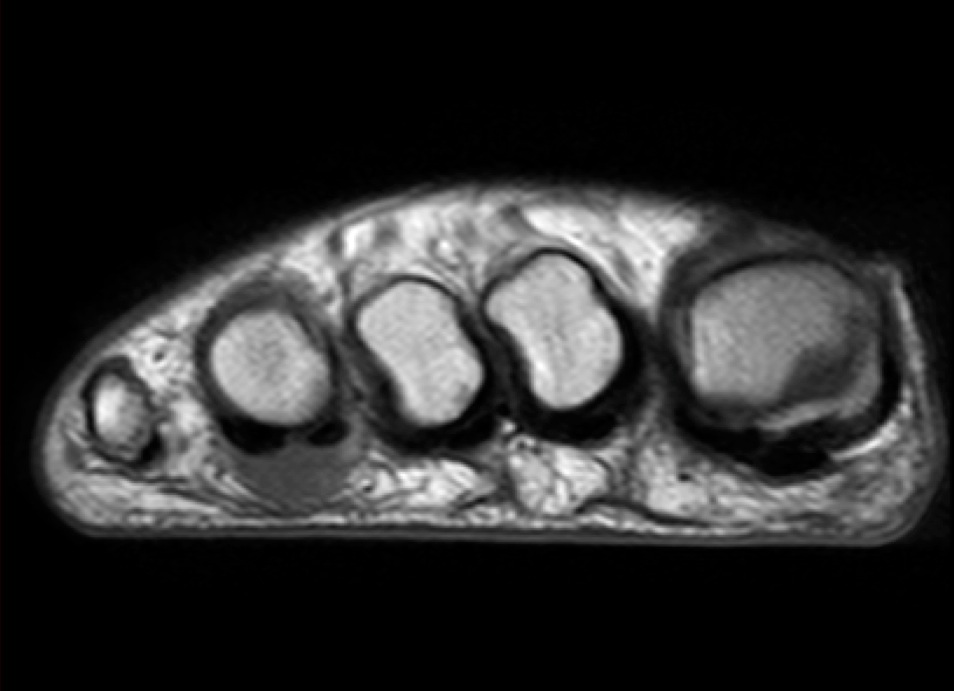

Figure 3 for case Advential bursitis

Figure 3